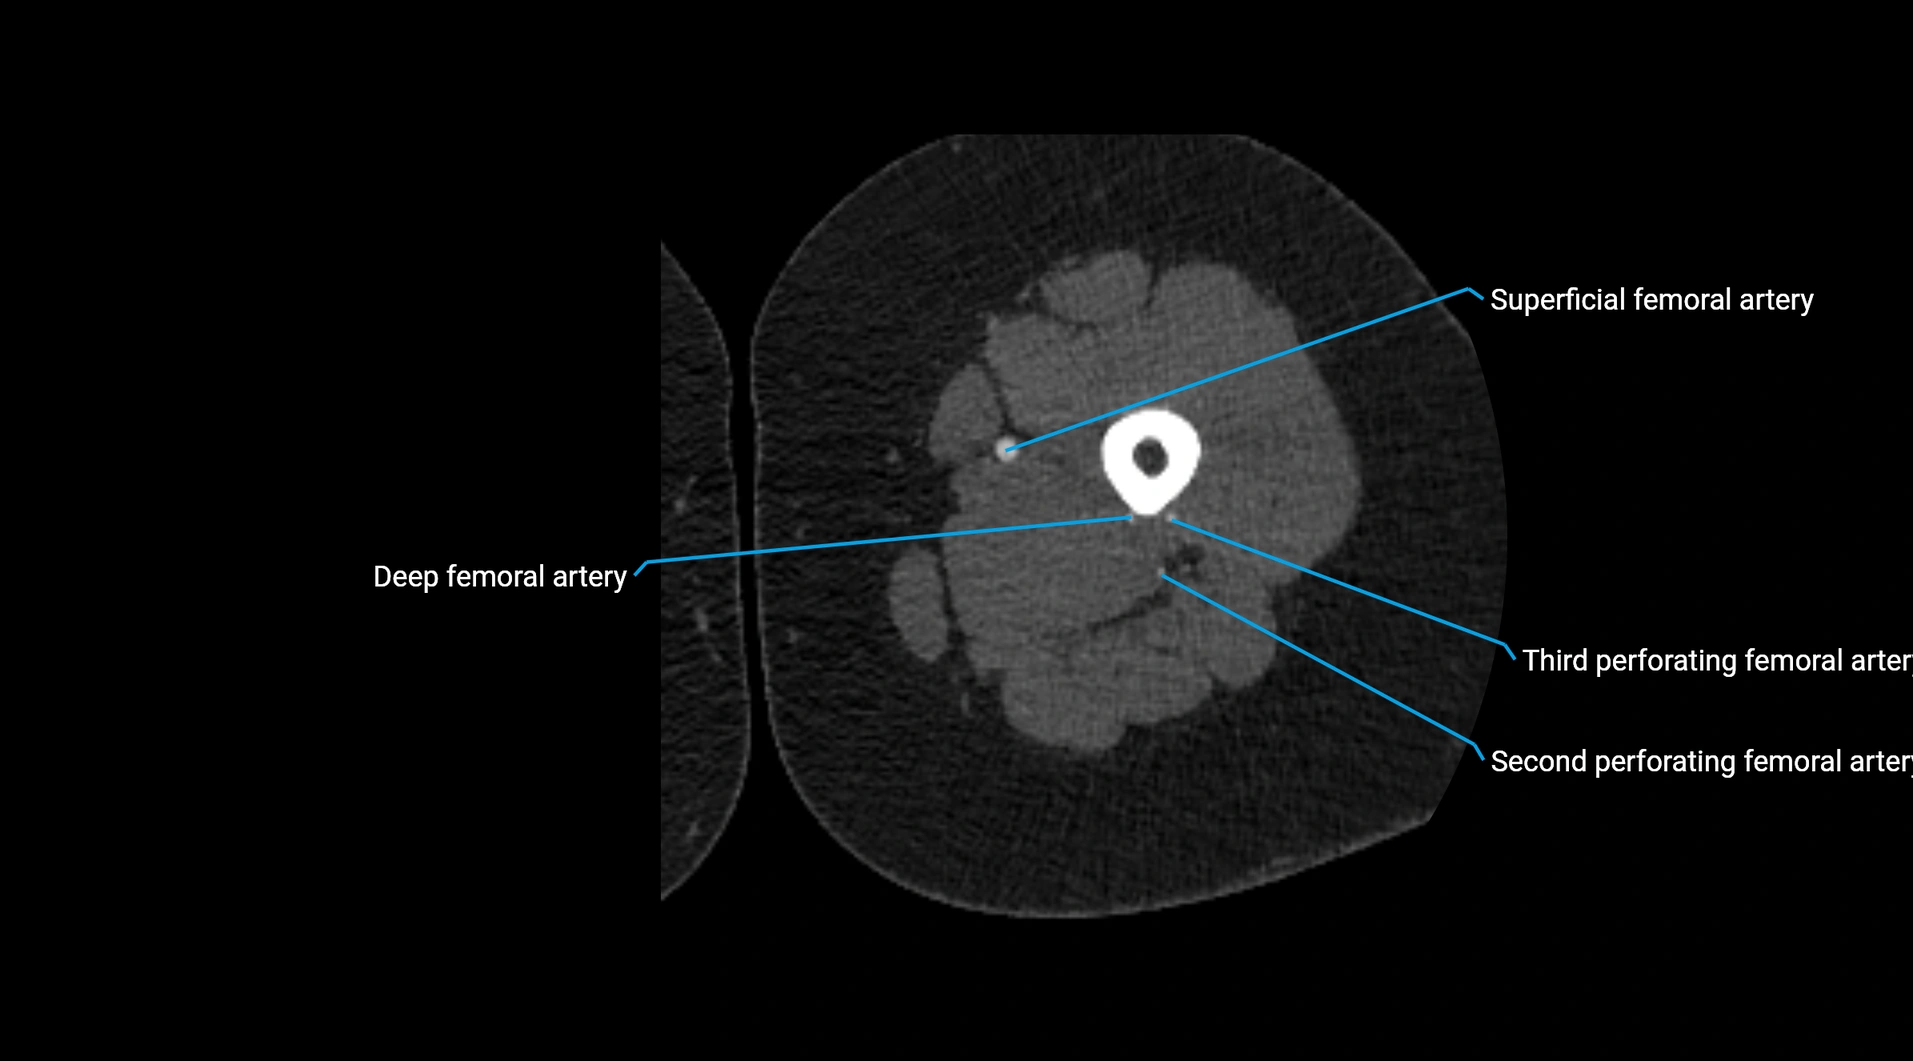

CT images

image